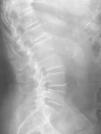

La espondilodiscitis lumbar (EDL) es una infección del cuerpo y el disco vertebral cuya clínica en fases iniciales se puede confundir fácilmente con otros cuadros de dolor lumbar de causa menor. Es necesario un elevado grado de sospecha clínica para evitar retrasar su diagnóstico, así como tener en cuenta la presencia de factores de riesgo que pudieran favorecer su desarrollo. La detección y el manejo precoces pueden evitar en gran parte la discapacidad que causa este cuadro. Se presentan dos casos clínicos de EDL asociados a estreptococos del grupo viridans y Enterobacter aerogenes, respectivamente, y se destacan, a propósito de éstos, los pasos clave necesarios para evitar un retraso diagnóstico.

Lumbar spondylodiscitis is an infection of the low back vertebral body and the intervertebral disc space. In early stages it must be differenciated from other minor causes of low back pain. Its diagnosis demands a high level of clinical suspicion, as well as taking into account any risk factor which could favour its development. Early detection and treatment prevent future disability. Two cases, related to Viridians Streptococi and Enterobacter aerogenes, respectively, are described in order to review the key steps to avoid delayed diagnosis.